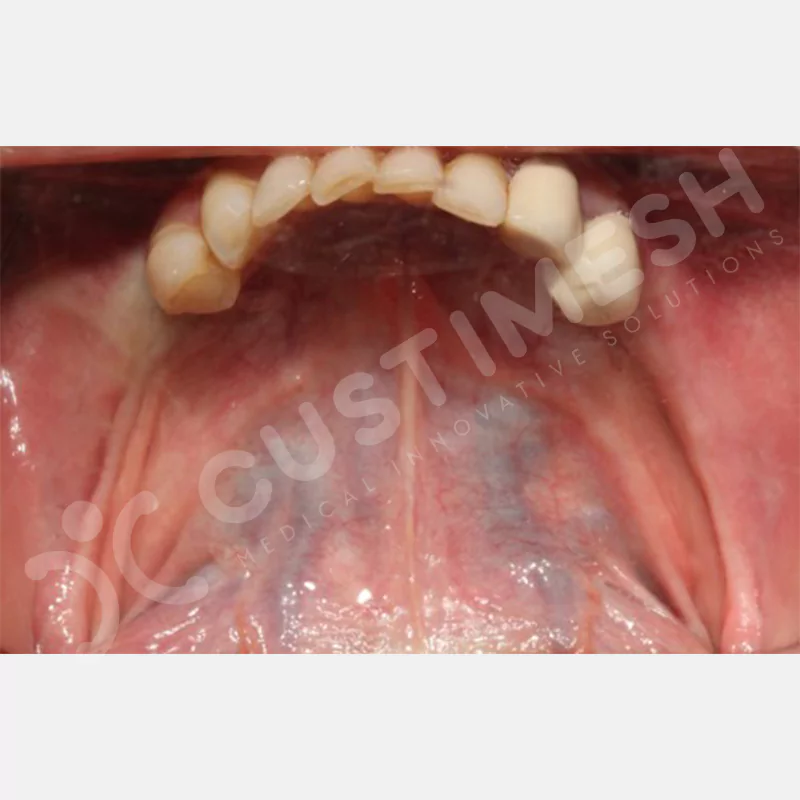

VAKA 1

VAKA 2

VAKA 3